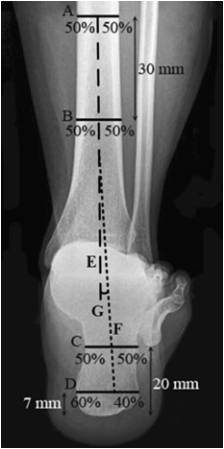

Saltzman 位 1. 确定胫骨长轴E 2. 确定跟骨长轴F – 距跟骨最低处7mm处做水平线C,分为3:2 – 距跟骨最低处20mm处做水平线D:分为1:1 – 正常足:0°~5° – 外翻足:5°~10° – 严重外翻足:>10° – 内翻足:0°~-10° – 严重内翻足:<-10° |